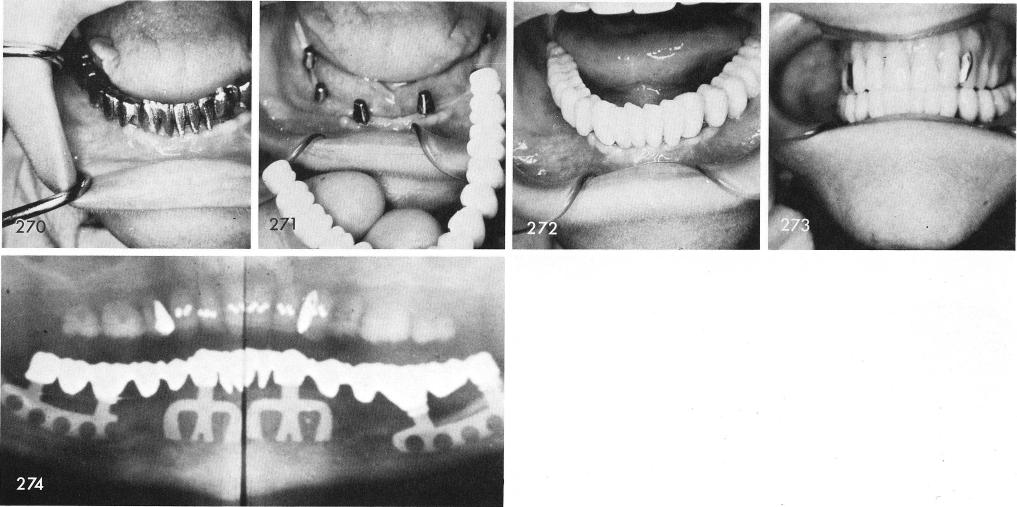

The patient presented herself with a lower denture which she was totally frustrated with, fig. 264. The ridge posteriorly and anteriorly was knife-edged and very shallow, figs. 265, 266. She was warned of a very good chance of a parethesia but she insisted that she did not care and would still rather have the implants, fig. 267. Posteriorly the blades had to go buccally. The tissues were sutured closed, fig. 268, and an immediate temporary acrylic splint was fabricated, fig. 269. Several more visits took place which included the fitting of the gold castings and the completed porcelain-fused to metal prosthesis was ready to be cemented, figs. 270, 271, 272, 273. The x-ray shows the well inserted bladevents. fig. 274.